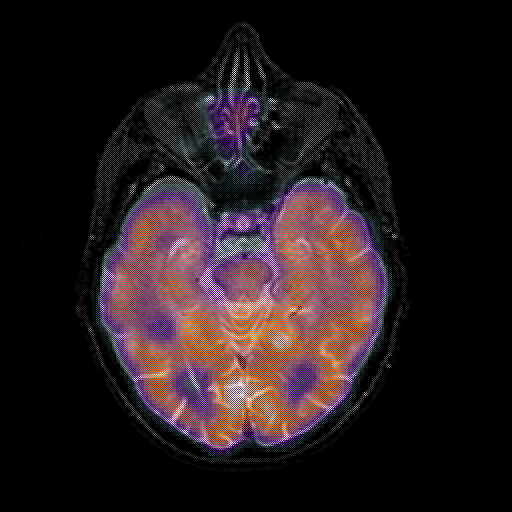

overlay 1: Slice 20

Slice 20

MRCBFCBF with

T1PDT2T1PDT2